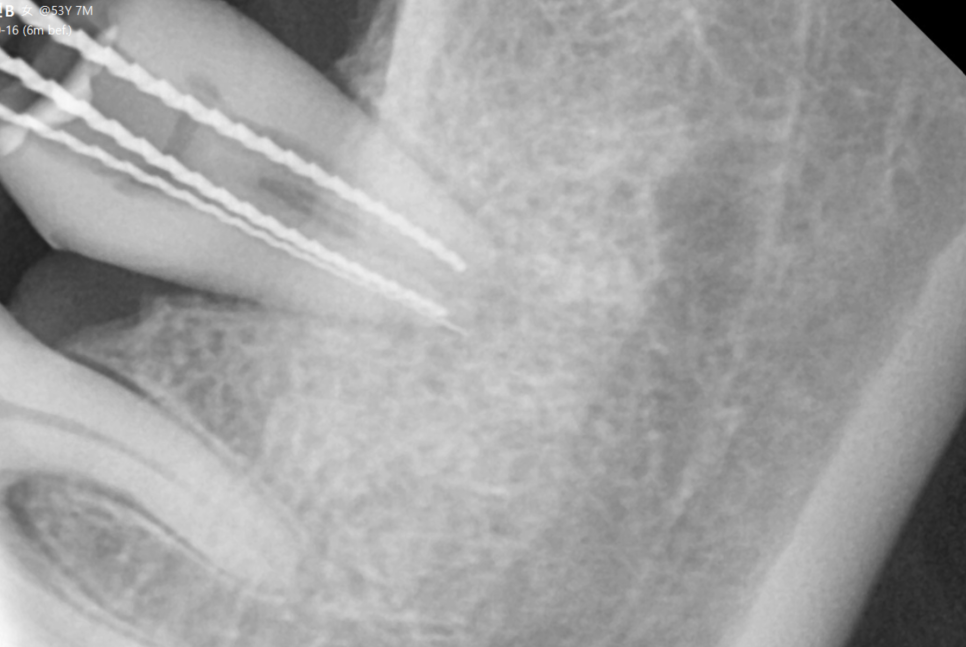

241022

x-ray를 찍어도 알 수가 없어요.

완전히 부러져 분리되기 전까지는 말이죠.